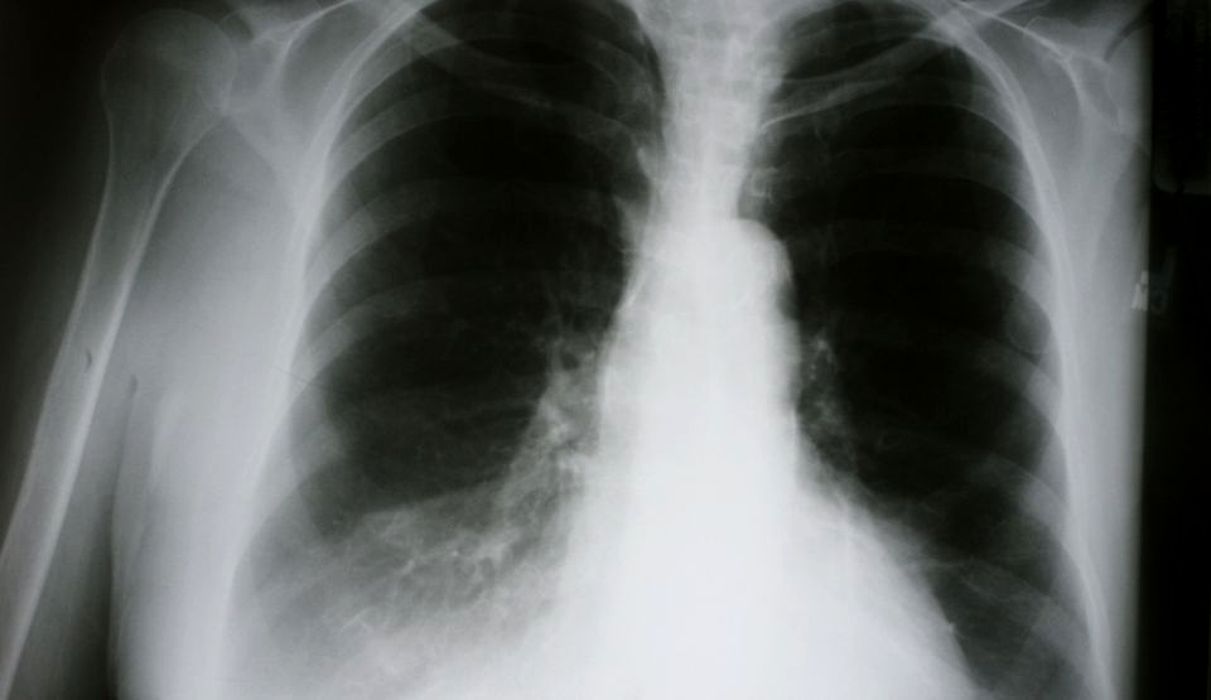

Insuficiența respiratorie în COVID-19 nu este cauzată, de obicei, de furtuna de citokine – studiu

Insuficiența respiratorie, unul dintre efectele majore ale bolii COVID-19, nu este declanșată în majoritatea cazurilor de așa-numita „furtună de citokine”. Un studiu efectuat de cercetători de la Școala de Medicină din cadrul Universității Washington, din […]